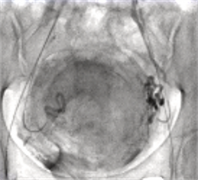

1、子宫动脉栓塞技术并发症:和操作相关(可避免) 导管导丝引起子宫动脉痉挛或夹层 穿刺部位并发症 子宫动脉栓塞错误的终点:未达终点、过度栓塞、异位栓塞...

卵巢动脉供血 卵巢是子宫动脉供应的最常见另外一个来源。Nikolic B et alJVIR. 1999; ...